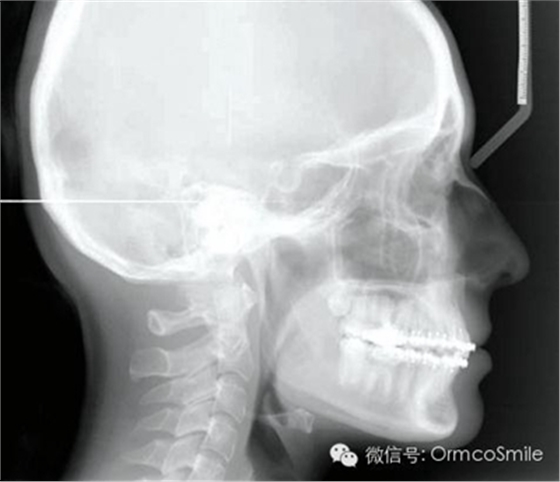

治療目標(biāo)為:遠(yuǎn)中移動上頜右側(cè)磨牙,達(dá)到安氏Ⅰ類尖牙、磨牙關(guān)系。治療前,拔除上頜左側(cè)第三磨牙,將一直徑2mm,長14mm的鈦骨釘植入上頜腭中縫,位于切牙孔后4-5mm,中線旁3-4mm。用1.3mm直徑的鉆助攻植入螺紋釘。一周之后,取印模并灌制模型,將螺紋釘?shù)念^部用蠟包圍,從螺紋釘上延伸出連接第一前磨牙的0.8mm的鋼絲??趦?nèi)試戴后,用光固化樹脂將從螺紋釘上延伸出的弓絲與上頜第一前磨牙粘接在一起,0.016*0.022英寸不銹鋼絲片段弓加鎳鈦推簧置于上頜第一磨牙和第一前磨牙間,每側(cè)250g力推動上頜磨牙向遠(yuǎn)中,磨牙到位后拍攝頭側(cè)位片。

經(jīng)測量,上頜第一磨牙遠(yuǎn)中移動3.5mm,達(dá)到磨牙Ⅰ類關(guān)系,同時壓低2mm,而第一前磨牙和上頜切牙沒有明顯的移動。上頜第一前磨牙有3°的輕度前傾,這可能是由于上頜只植入了1顆螺紋釘?shù)脑?,作者分析采用兩顆螺紋釘可以減少這種副作用。在上頜磨牙遠(yuǎn)中移動過程中,下頜平面角減少了1°,且其持續(xù)到正畸治療結(jié)束。上頜牙弓寬度有輕度擴(kuò)大。